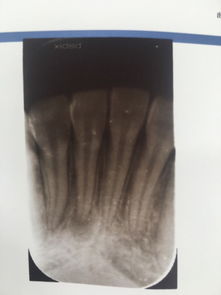

導(dǎo)致牙根發(fā)炎的因素有很多,出現(xiàn)的時候要及時進(jìn)行治療。那么,牙根發(fā)炎怎么辦?

牙根炎癥的存在,會反復(fù)腫痛,影響牙齒的咀嚼功能,嚴(yán)重會造成牙的喪失。這樣不僅會影響消化功能,而且在童年時期會影響面部的發(fā)育。此外,有的牙根炎癥進(jìn)一步發(fā)展會導(dǎo)致全身其它器官的病變。

5、如果牙根發(fā)炎的比較厲害引起牙髓炎或根尖周炎,咨詢醫(yī)生是否需要做根管治療術(shù)。